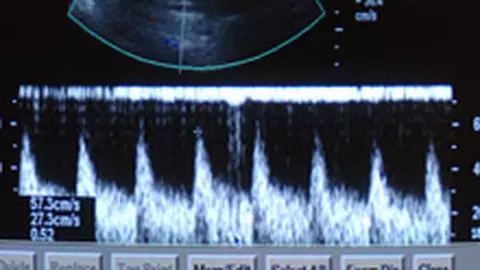

Placenta previa reprezinta o situatie in care placenta se afla in partea de jos a uterului, acoperind cervixul (canalul de nastere).